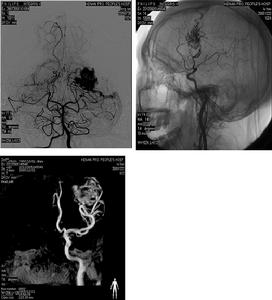

7、選擇性全腦血管造影(DSA)可了解AVM的部位、供血動脈、畸形血管團大小以及引流靜脈,了解是否伴有動脈瘤、靜脈瘤、動靜脈瘺及腦盜血情況。必要時加做頸外動脈造影,以了解是否有頸外動脈參與供血。

⑥腦血管造影。是診斷動靜脈畸形的重要手段。是必須進行的檢查方法。不僅能確定診斷而且還為治療提供依據。造影常顯示不規則曲張扭纏的畸形血管團,並可顯示供血動脈和引流靜脈。引流靜脈常在動脈期即可過早顯影。但仍有一部分小的或隱匿型動靜脈畸形不能被造影發現(約11%)。數字減影、放大造影、連續攝片、立體血管造影等更有助於診斷。